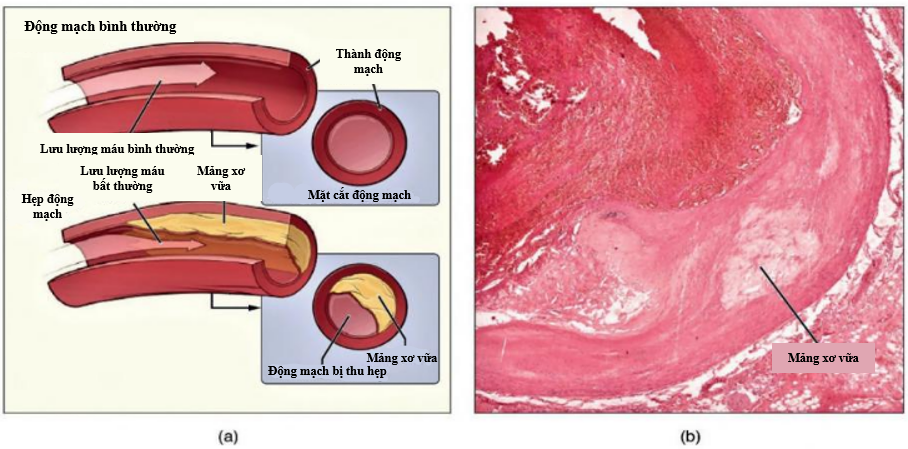

Hệ tuần hoàn là hệ cơ quan gồm mạch máu, máu và bạch huyết, tạo thành vòng tuần hoàn lớn và nhỏ giúp vận chuyển các chất dinh dưỡng, oxy đến mô, cơ quan và lấy các chất sau chuyển hóa, CO2, v.v. đào thải khỏi cơ thể. Theo Tổ chức Y tế Thế giới (WHO), ước tính ở người trưởng thành, tổng chiều dài các mạch máu là hơn 160.000 km, đủ để cuốn 4 vòng quanh xích đạo Trái Đất. Chính vì là hệ thống lớn của cơ thể và có vai trò rất quan trọng nên những tổn thương, bệnh lý liên quan đến hệ thống tuần hoàn là rất hay gặp phải và ảnh hưởng nhiều đến toàn thân, đồng thời là nguyên nhân gây tử vong hàng đầu trên thế giới. Chỉ tính riêng năm 2019, có khoảng 17,9 triệu người tử vong vì bệnh tim mạch, chiếm 32% tổng số ca tử vong trên toàn thế giới. Tại Việt Nam, bệnh tim mạch bao gồm đột quỵ và bệnh tim thiếu máu cục bộ góp phần gây ra tỷ lệ tử vong cao. Nguyên nhân chính của những trường hợp tử vong liên quan đến bệnh lý tim mạch là do huyết áp, tình trạng vữa xơ động mạch (Hình 1), phình mạch, rối loạn nhịp, bệnh động mạch ngoại vi, v.v.

Phẫu thuật ghép mạch được sử dụng rộng rãi để điều trị những trường hợp tổn thương gây hẹp mạch nghiêm trọng (> 65% đường kính lòng mạch) hoặc thay thế đoạn mạch do phình mạch hoặc ghép tạng. Các mạch ghép được được lựa chọn thường là tự thân, đồng loài, dị loài hoặc nhân tạo. Tuy nhiên, việc sử dụng các mạch máu tự thân không phải lúc nào cũng thuận lợi và mạch được lựa chọn chủ yếu là tĩnh mạch – cơ quan thường bị xơ hóa theo thời gian (< 10 năm). Ghép mạch máu đồng loài hay từ mạch in bằng công nghệ 3D là hướng lựa chọn tốt với những hy vọng như mạch có thể phát triển theo kích thước mô tạng, tuy nhiên cũng gặp khó khăn do tương thích miễn dịch. Mạch máu nhân tạo ví dụ như mạch Dacron và Teflon (expanded polytetrafluoroethylene – ePTFE) được sử dụng phổ biến trong điều trị, tuy nhiên kích thước nhỏ nên hiệu quả thấp. Bên cạnh đó, mạch nhân tạo có thể gặp biến chứng như chảy máu, hẹp lòng đoạn mạch cấy ghép, nhiễm trùng vết thương, phình mối nối, dị ứng, phản ứng miễn dịch, đặc biệt là sẽ hẹp tương đối khi cơ thể còn phát triển, v.v. Vì vậy, đến nay chưa có mạch nhân tạo hoàn hảo.